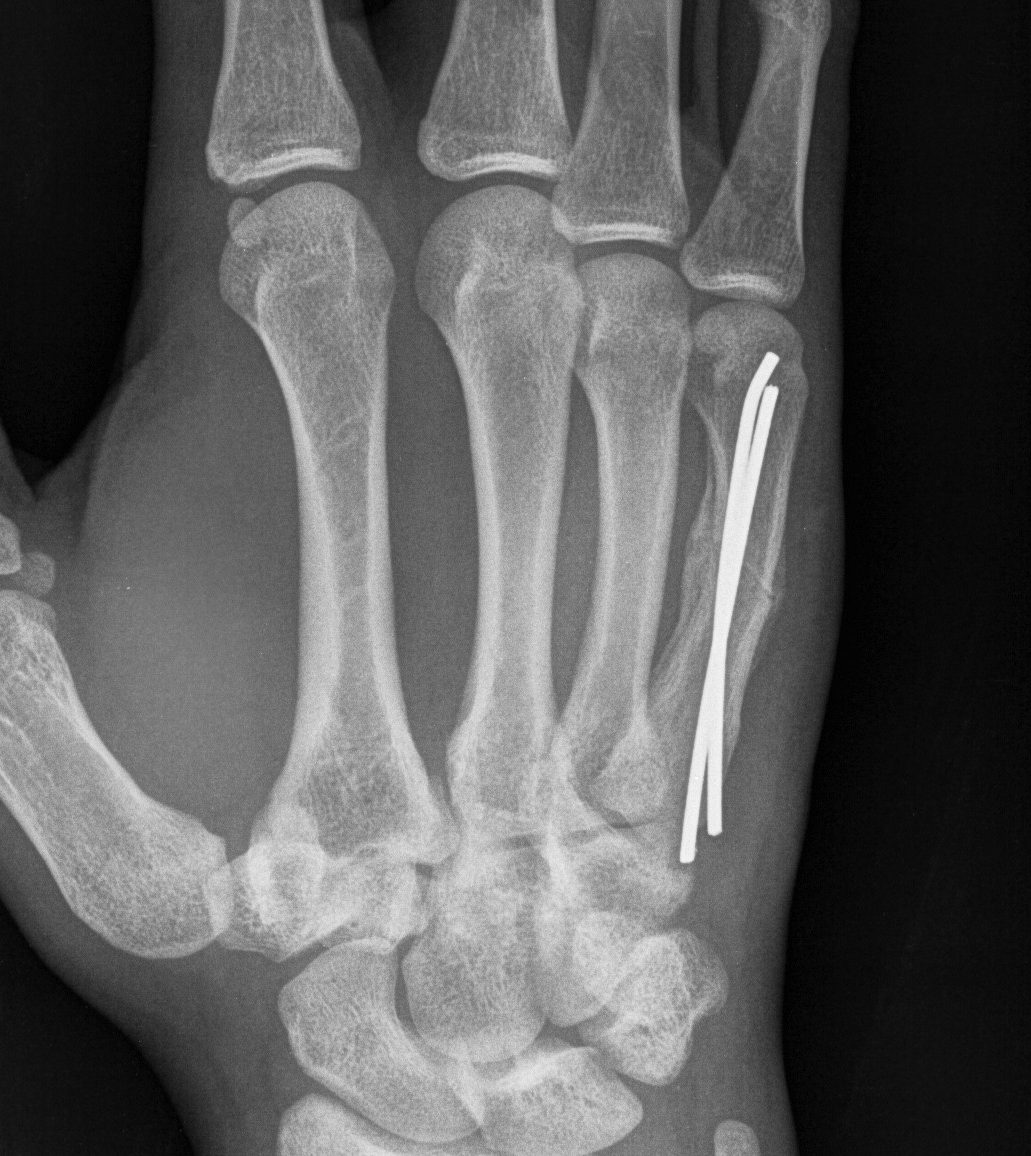

Operative Management

Options

- plate

- lag screws (if spiral fracture)

- intramedullary wires